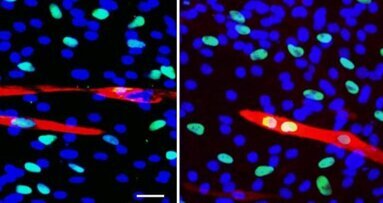

L’équipe de Gordana Vunjak-Novakovic (de l’université Columbia, New York) a réussi à ensemencer un os de veau, débarrassé de ses cellules, avec des cellules souches adultes humaines de la moelle osseuse.

Préalablement découpé aux dimensions voulues, cet os a été placé dans un bioréacteur fait, lui aussi, sur mesure. Le bioréacteur a apporté en profondeur les nutriments nécessaires à la prolifération et à la différenciation des cellules osseuses. Au bout de cinq semaines, un os vivant avait remplacé la structure inerte initiale. Guy Daculsi de l’Inserm considère que le processus est maintenant au point : « Des sociétés se positionnent déjà à l’étranger pour reproduire des structures osseuses plus complexes en bioréacteur. En Europe, le projet “Reborne”, coordonné par l’Inserm, a lancé cinq essais cliniques de reconstitution osseuse chez l’homme, pour les chirurgies orthopédique et maxillo-faciale ».